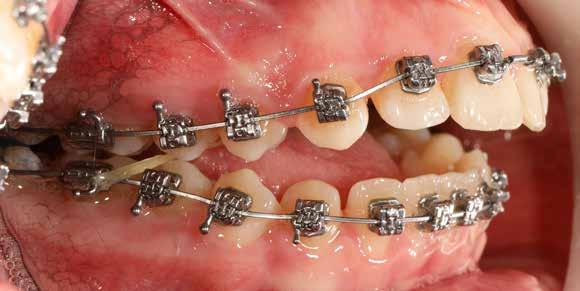

A Pitts21-es fix készülékes kezelés során a harapásemelőket a felső nagyőrlő fogakra ragasztottuk, hogy a felső molárisok intrúziójával segítsék a harapás zárását (8. kép) Ún. keresztharapásos, majd később normál class 2-es gumihúzással (9–10. képek), továbbá az elülső fogakon alkalmazott ún. Rainbow harapás-záró gumihúzással (11. kép) korrigáltuk a jobb oldali teljes premolárisnyi distal-harapást, valamint az elülső nyitott harapást.

6 hónap után a nyitott harapás már nagyjából összezárásra került (12. kép)! A gumihordás a kezelés teljes hosszában folyamatos, éjjel-nappal, 22-24 órában az étkezések és az utánuk történő fogmosás kivételével.

A fix fogszabályozó készülék mindössze 16 hónapos kezelés után került eltávolításra! Páciensünk legnagyobb örömére állcsontműtét nélkül sikerült mind az arcesztétikai, mind a funkcionális rehabilitáció (13–18. képek)